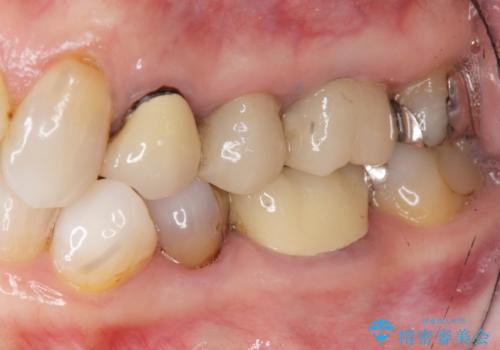

[ 深い虫歯・根管治療・セラミッククラウン ]複合した問題を持った虫歯治療

![[ 深い虫歯・根管治療・セラミッククラウン ]複合した問題を持った虫歯治療の症例 治療前](https://seimitsushinbi.jp/wp/wp-content/uploads/2022/09/b464b4c5c3053a5fc84212fb664a039f-500x350.jpg?v=1663667230)

![[ 深い虫歯・根管治療・セラミッククラウン ]複合した問題を持った虫歯治療の症例 治療後](https://seimitsushinbi.jp/wp/wp-content/uploads/2022/09/bd017e5dbd742f9bb33f09d39c8f1b52-500x350.jpg?v=1663667487)